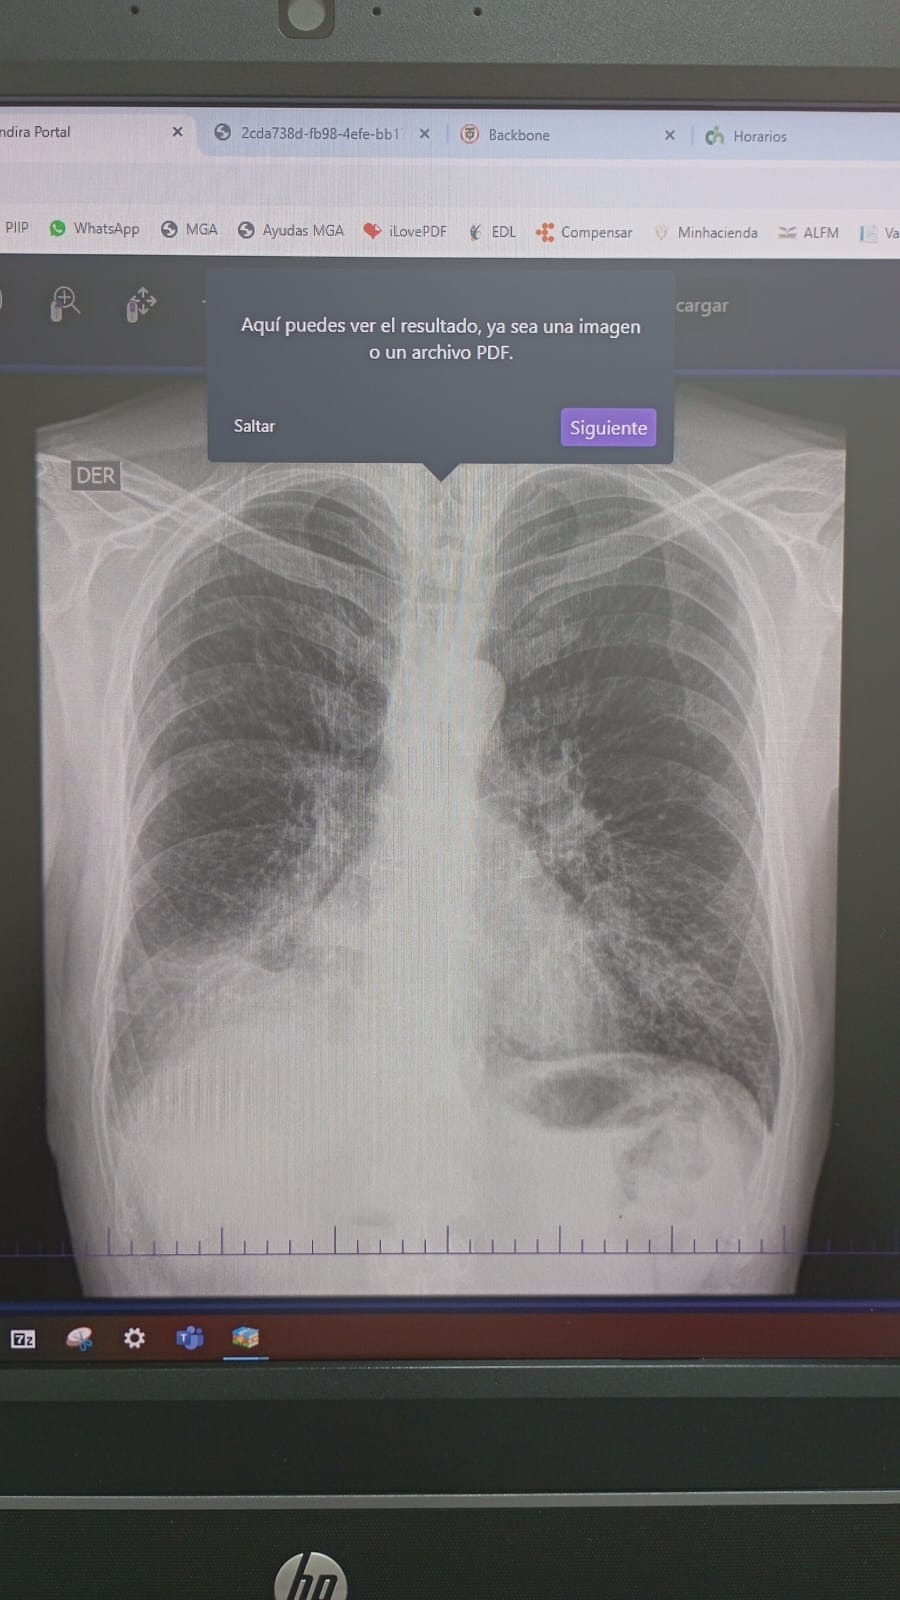

In December of 2024, what started as a small cough became our worst nightmare. With limited access to health care, we paid what exams we could out of pocket. Scans confirmed a tumor, this time on his bronchus, where air flows. This tumor was slowly suffocating my dad. He would have coughing episodes so bad he could barely breathe.

My dad had to leave the country in May and 3 months later he has yet to start any treatment. Due to Colombia's healthcare system, that means months of waiting for each test with insurance. While he waited, the cancer spread to his kidney. Now to his brain. Two tumors are causing him to loose feeling from the left side of his face, his mouth, and his eye. He is at risk for paralysis.

- Diagnostic tests and imaging (CT scans, MRIs, etc.)

- Pruebas diagnósticas e imágenes (tomografías, resonancias, etc.)